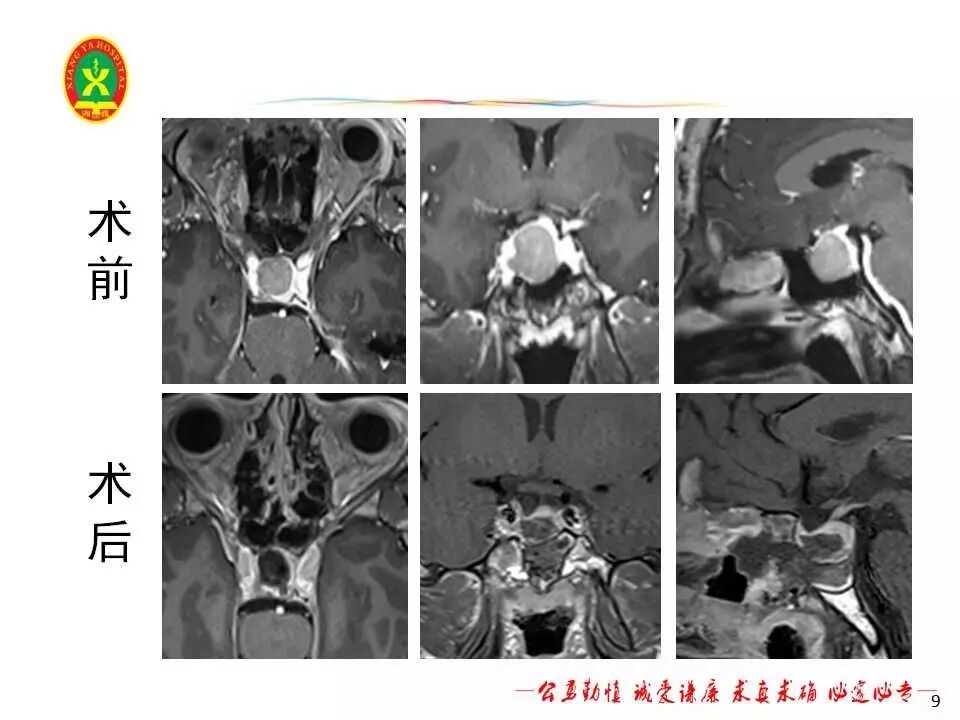

何**,男,36岁,生长激素大腺瘤,行神经内镜下经鼻蝶垂体腺瘤切除术。

该患者术中见鞍底骨质变薄,部分缺损(约0.5×0.5cm大小),垂体位于肿瘤后上方,术中肿瘤全切。患者术后恢复良好,无脑脊液漏、尿崩及电解质紊乱。术后复查生长激素较术前明显下降(见表2),甲状腺轴及性腺轴正常。术后MRI提示肿瘤全切,垂体结构保留完好。患者术后3天出院,嘱患者3个月后我院垂体腺瘤联合门诊复诊。